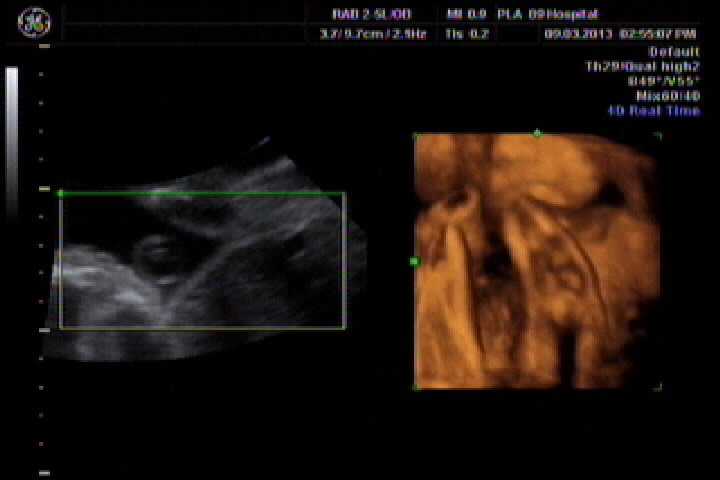

今天刚做了四维彩超,刻了光盘,但不会看,想请专业认识帮我看看胎儿性别,胎儿27周又5天 点击展开 匿名用户 2013-03-10 00:01 为您推荐: 其他回答 你这个大夫估计就是骗你钱呢,打的什么图像,宝宝一点没照到,而且图像特别虚,上面的图片只是羊水和脐动脉,一点实质性内容都没有 宫和玉_XzIQ 2013-03-10 10:16 汗。。。 说了违法。 而且网上的人说了你就信啊。 忽悠你不要钱的。 孟觅翠_RspR 2013-03-10 00:19 相关问题 孕晚期如何测胎儿性别怎样从四维彩超数据看胎儿性别? 多久怀孕可以判断胎儿性别,怎么判断我现在孕7周 14周B超数据如何来判断胎儿性别 前壁,双顶径27,股骨长13,能看出男孩女孩吗?